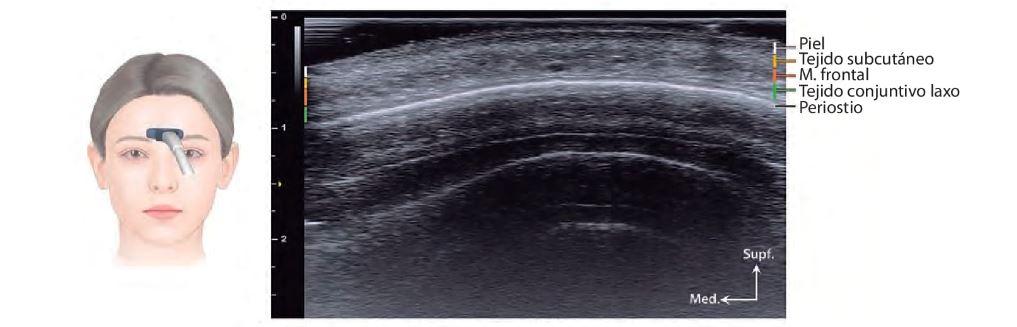

La cara y el cuello están compuestos por cinco capas anatómicas: piel, tejido subcutáneo, SMAS, ligamentos de retención y fascia profunda. La ecografía permite visualizar estas capas en tiempo real, facilitando la identificación de estructuras críticas como vasos, nervios y compartimentos grasos.

El conocimiento del grosor de la piel, que varía entre regiones como el párpado superior (0,38–0,80 mm) y la punta nasal (1,22–2,01 mm), es fundamental para ajustar técnicas de inyección y procedimientos quirúrgicos. Además, la localización precisa de glándulas salivales (parótida, submandibular y sublingual) mediante ecografía evita complicaciones durante intervenciones en la región mandibular y cervical.